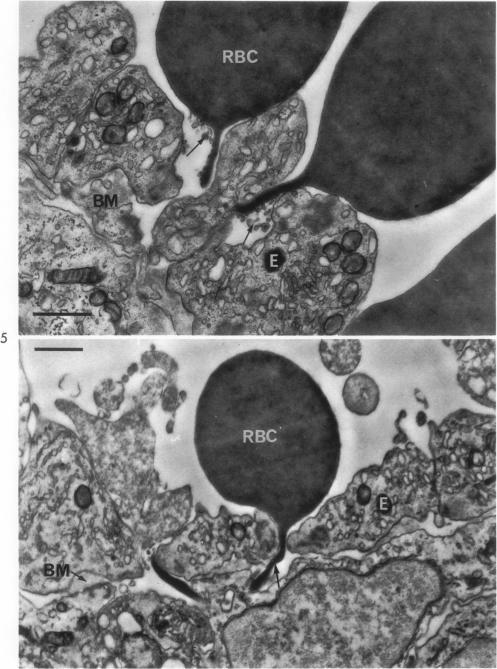

Studies of catecholamine shock. II. An experimental model of microangiopathic hemolysis.

Am J Pathol. 1969 Aug;56(2):177-200.